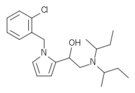

| Opioid peptides | Skeletal molecular images |